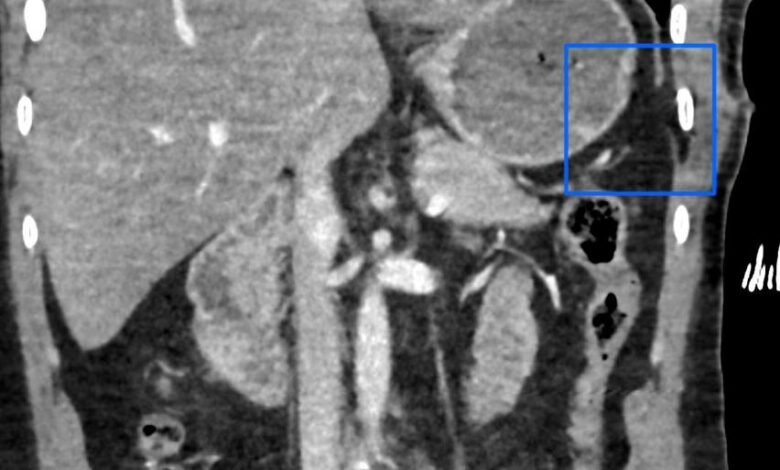

تمكن مستشفى الإيمان العام عضو تجمع الرياض الصحي الأول من إنقاذ حياة شاب عشريني تعرض لإصابة في الجهة اليسرى من الصدر؛ أدت إلى حدوث قطع في الحجاب الحاجز، وثقب في القولون المستعرض.

حيث قام الفريق الطبي بقيادة رئيس قسم الجراحة العامة استشاري الجراحة والمناظير د. سعد الدوسري، واستشاري الجراحة العامة د. ريان الحوشان بإجراء جراحي عاجل تم خلاله إصلاح الإصابات المذكورة عن طريق المنظار الجراحي عبر ثلاثة فتحات صغيرة بحجم 5 مم، تكللت بالنجاح -ولله الحمد-.

الجدير بالذكر أن مثل هذه الإصابات عادة يتم إجراؤها عن طريق الشق الكامل للبطن، ولكن إستطاع الفريق الطبي بمستشفى الإيمان العام تفاديه -بتوفيق من الله-؛ حيث ساهمت خبرة الفريق الطبي وتوفر الإمكانيات والتقنيات الحديثة في المستشفى من إجراء العملية وفق أفضل الممارسات الطبية والتي ساهمت بتحسن حالة المريض في فترة وجيزة -ولله الحمد-.